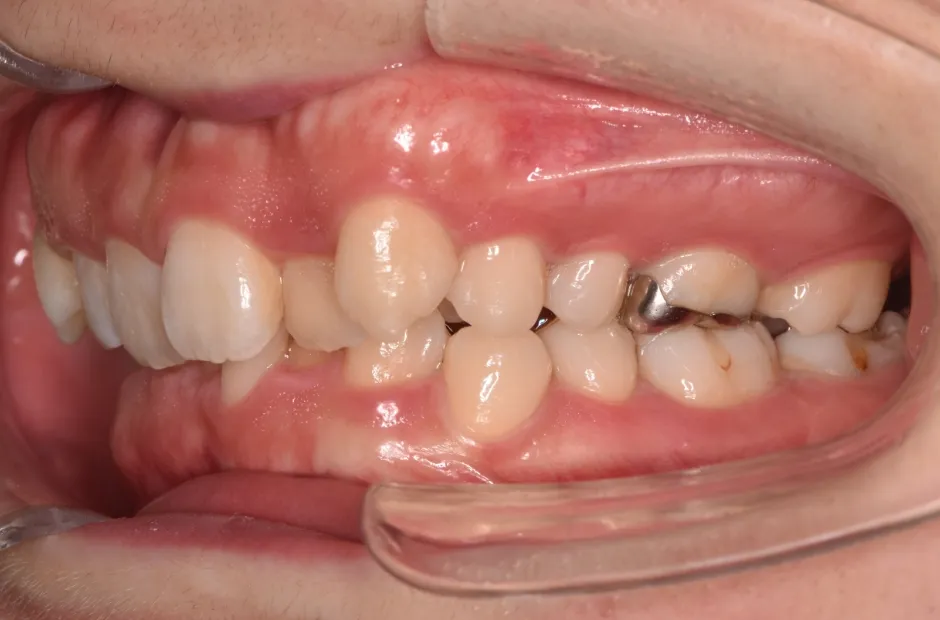

叢生

| 診断名・主訴 | 叢生 |

|---|---|

| 年齢・性別 | 43歳・女性 |

| 治療期間・回数 | 2年7か月 27回 |

| 治療に用いた主な装置 | 舌側矯正 |

| 抜歯部位 | 両顎4,4 |

| 治療費 | 100万円(税抜) |

| リスク・副作用 | 装置による違和感・疼痛・歯肉退縮・歯根吸収・虫歯のリスクなど |